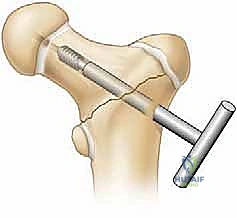

3. التثبيت الداخلي (Internal Fixation)

تُستخدم أدوات تثبيت خاصة بالأطفال. في الأطفال الأكبر سناً، تُستخدم مسامير مجوفة (Cannulated Screws) يتم إدخالها بدقة فائقة. يحرص الدكتور هطيف بصرامة على عدم اختراق صفائح النمو بالمسامير إلا إذا كانت الضرورة القصوى تقتضي ذلك (وفي هذه الحالة تُستخدم مسامير ملساء لتجنب إعاقة النمو).

ج. تشوه الورك للداخل (Coxa Vara)

يحدث عندما يلتئم الكسر بزاوية غير طبيعية (زاوية عنق الفخذ تصبح أقل من الطبيعي). يؤدي ذلك إلى عرج دائم أثناء المشي. التثبيت الجراحي القوي والمحكم هو الحل الأمثل لمنع هذا التشوه.